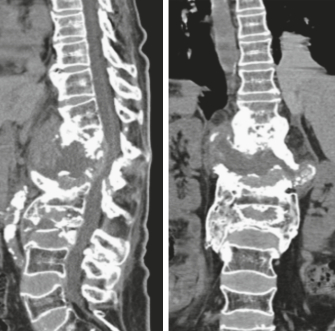

Auswirkungen auf die Wirbelsäule

Eine Neuroarthropathie an der Wirbelsäule endet praktisch immer in einer wirbelsäulenchirurgischen Stabilisation. Manchmal, so Koch und Geng, muss der zerstörte Bereich durch Transplantation von Knochen oder Implantation eines Cages (Platzhalters) komplett überbrückt werden. Häufig muss die Wirbelsäule bis zum Becken/Kreuzbein hinunter stabilisiert werden.